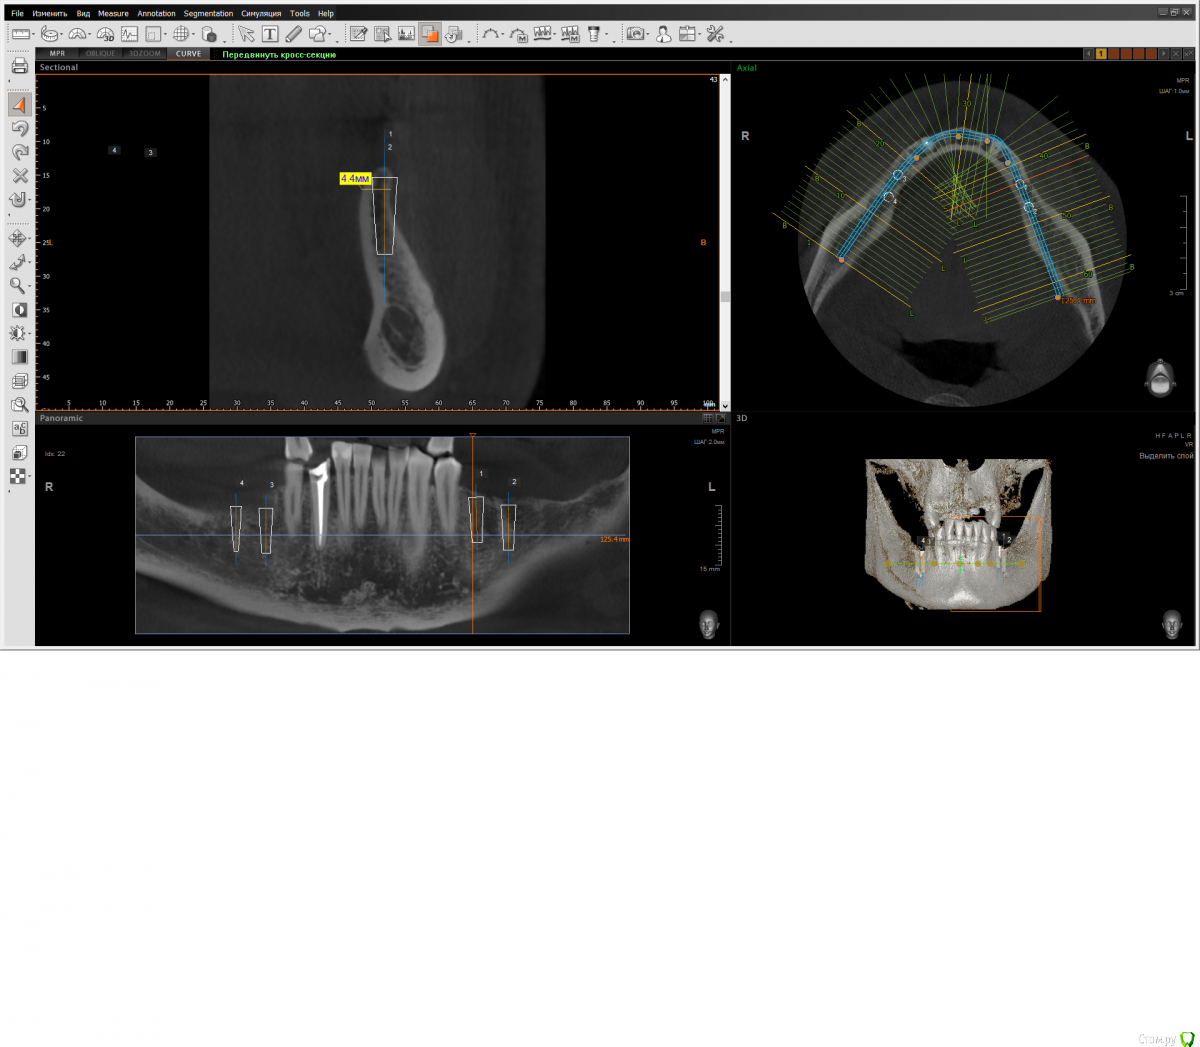

wladdX Опубликовано 10 марта, 2020 Поделиться Опубликовано 10 марта, 2020 Узковато? Ссылка на комментарий

Doctor Vlad Опубликовано 10 марта, 2020 Автор Поделиться Опубликовано 10 марта, 2020 а что означает название темы? то что ширины кости маловато! для привлечения внимания) Ссылка на комментарий

Doctor Vlad Опубликовано 10 марта, 2020 Автор Поделиться Опубликовано 10 марта, 2020 Узковато?угадал)! Ссылка на комментарий